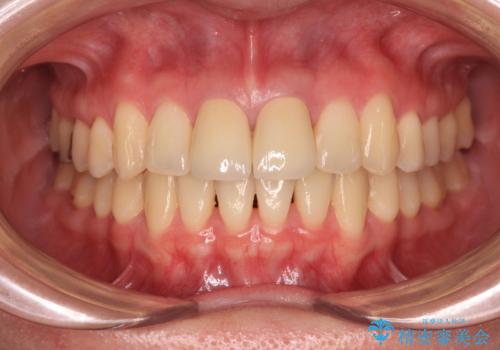

変色した前歯 オールセラミッククラウンにより審美歯科治療

- 神経を取り除いたことで経年変色した前歯2本を気にして来院された患者様です。

根管治療を行う必要はないと判断し、双方の歯にグラスファイバーを含有した土台を植立してオールセラミッククラウンにて補綴することとしました。

色調が周囲の歯とアウトともに、表面のつぎはぎや穴を封鎖した際の段差などが解消され、天然歯のような感触となりました。